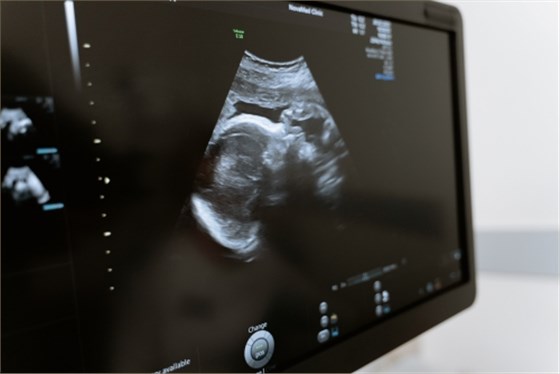

上肢血管超聲檢查是通過(guò)超聲檢查血管壁、血管內(nèi)血流情況的技術(shù)。一般情況下,上肢血管超聲檢查可用于診斷動(dòng)脈硬化、靜脈狹窄、動(dòng)靜脈瘺、血栓閉塞性脈管炎、靜脈血栓形成等疾病。